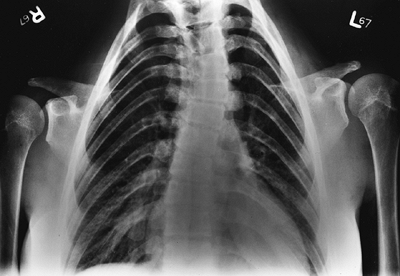

the neonatal period (the most severely affected age group). Cardiac

features include hypospadias and epispadias. The skeletal features are

(acromesomelic) in combination with a normal spine (76). This distal shortening is the opposite of that seen in achondroplasia (77,78,79).

The chest is narrow. The ligaments are lax, and there is often

significant genu valgum. The proximal tibial epiphysis is often